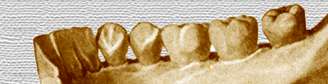

Porción

alveolar |